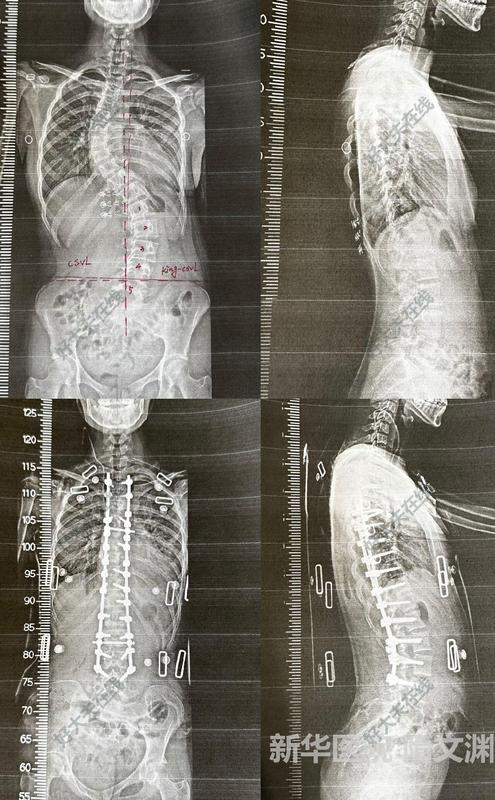

日常工作-2例青少年特發(fā)性脊柱側(cè)凸患者手術(shù)

近幾年脊柱側(cè)凸比例逐年增加,上升之快已成為繼近視、肥胖后危害青少年健康的“第三大殺手”。往往近視和肥胖,父母會(huì)早期覺察,而且中小學(xué)生每年查體中也都會(huì)常規(guī)體檢,早發(fā)現(xiàn)后也會(huì)早期及時(shí)干預(yù)。北京協(xié)和醫(yī)院骨科在手術(shù)治療青少年特發(fā)性脊柱側(cè)凸方面積攢了豐富的經(jīng)驗(yàn),手術(shù)創(chuàng)傷小、出血少、手術(shù)時(shí)間短,并發(fā)癥少,術(shù)后患者恢復(fù)快,矯形效果良好,患者術(shù)后滿意度高。來看看被骨科屆定義為“金字塔尖”的高難度手術(shù),下面以王升儒副教授的兩例日常病例患者為例,看看脊柱側(cè)凸矯形手術(shù)在協(xié)和醫(yī)院骨科是如何常規(guī)化開展的。小何姑娘(化名),今年12歲,發(fā)現(xiàn)背不平1年,就診于我院,排除手術(shù)禁忌后,在全麻下行后路T9-L3每節(jié)段關(guān)節(jié)突截骨松解、脊柱側(cè)凸矯形內(nèi)固定、植骨融合術(shù)(T8-L3),目前患者恢復(fù)好,四肢活動(dòng)良好,復(fù)查X線提示內(nèi)固定物位置良好,矯形滿意。矯形度數(shù)從術(shù)前的46°減少至6°,患者術(shù)后體態(tài)明顯改變,如獲新生。同樣來到北京協(xié)和醫(yī)院骨科治療青少年特發(fā)性脊柱側(cè)彎的還有小張同學(xué),今年12歲,無意中發(fā)現(xiàn)背部不平半月余。多方打聽后來到北京協(xié)和醫(yī)院骨科王升儒副教授門診,積極進(jìn)行術(shù)前檢查、檢驗(yàn)、準(zhǔn)備,排除手術(shù)禁忌癥后,在全麻下行脊柱后路經(jīng)關(guān)節(jié)突截骨(T6-L3Ponte截骨)、側(cè)凸矯形、內(nèi)固定、植骨融合術(shù)(T2-L4)。術(shù)后第二天查房時(shí),小張就激動(dòng)地說,自己明顯感覺體態(tài)更好了,能正常躺平睡覺了。來看看她術(shù)前術(shù)后的影像學(xué)對(duì)比。出院時(shí),張同學(xué)還俏皮地說,感謝協(xié)和醫(yī)院骨科讓她增高不少。